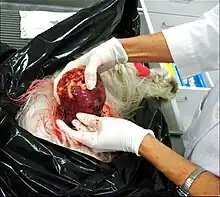

Rarely, cryptorchidism is due to the presence of a congenital testicular tumor such as a teratoma, which has a tendency to grow large.[28]